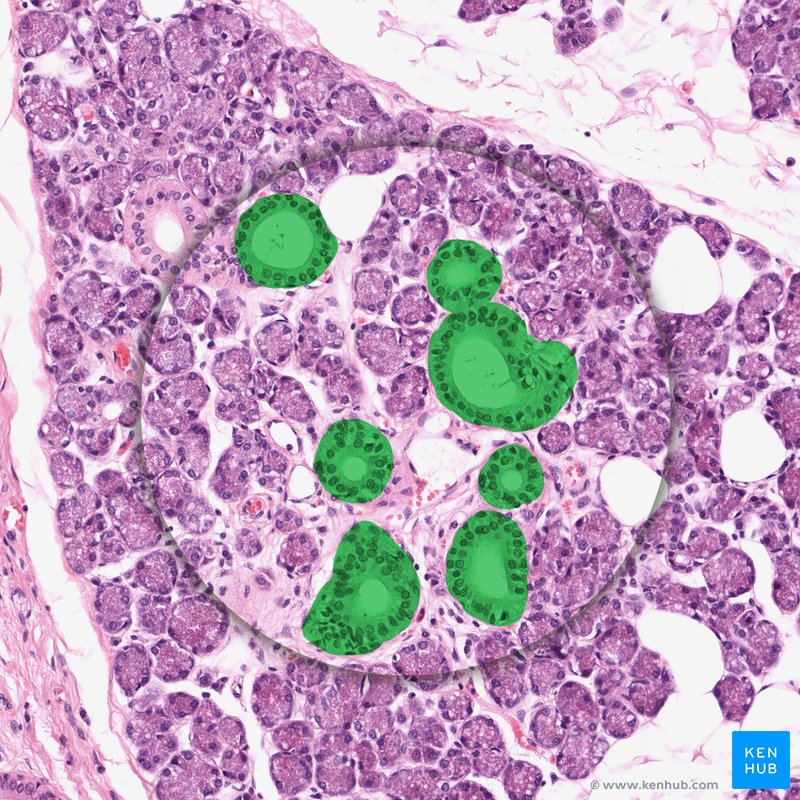

Accessory Organs Of Digestive System . Chemical digestion in the small intestine relies on the activities of three accessory digestive organs: Chemical digestion in the small intestine relies on the activities of three accessory digestive organs: Learn about the liver, gallbladder, and pancreas, the major accessory organs of digestion that secrete substances for chemical digestion in. Find out how bile, enzymes, and buffers help break down lipids, proteins, and carbohydrates in. Your digestive system is a network of organs that help you digest and absorb nutrition from your food. Accessory organs of digestion are organs that secrete substances needed for the chemical digestion of food but through which food does. The liver, pancreas, and gallbladder (figure 21.7.1). These accessory organs of digestion play key roles in the digestive process. The digestive role of the liver is to. The salivary glands, liver and gall bladder, and the pancreas aid the processes of ingestion, digestion, and absorption. Learn about the digestive roles, histology, and functions of the liver, pancreas, and gallbladder.